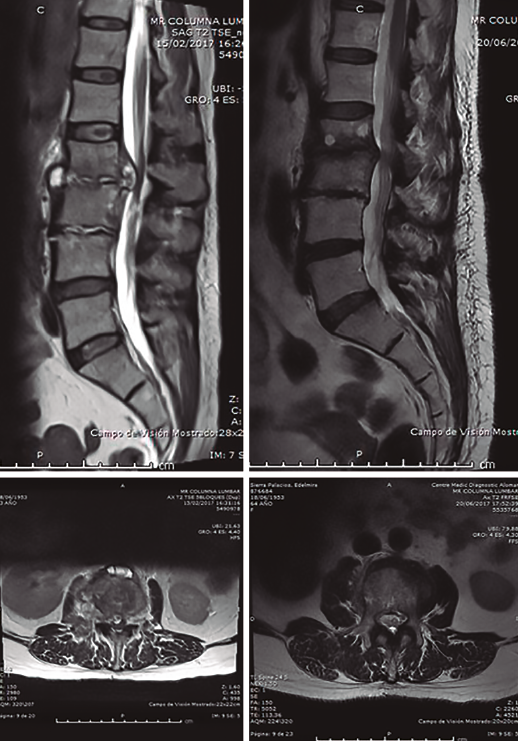

La paciente reingresó a los 3 meses del inicial, asintomática y con marcadores normales (Figura 5).

Figura 5. Resonancia magnética (RM) a los 3 meses del diagnóstico e inicio de tratamiento, comparando cortes sagitales y axiales de la RM inicial y final. Claro cambio en las imágenes, con desaparición de la “masa líquida” paravertebral y liberación del espacio intratecal.